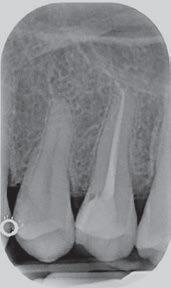

The third step of the treatment consisted of the crown lengthening, necessary to expose an adequate part of the root to obtain, after healing, the correct adhesion of the composite for the pre-prosthetic restoration and the successive prosthetic rehabilitation.

After the surgical flap elevation of the tissue and the bone remodeling, the flap was repositioned apically and sutured with a vertical mattress suture anchored in the periosteum (Figs. 5-6). The suture was removed after 7 days (Fig. 7).

glass fibre Figure 3: Root canal therapy completed under proper isolation. Figure 4: Radiography of completed root canal therapy and reconstruction made completely in glass hybrid cement. Figure 5: Clinical crown lengthening with a minimally invasive technique without mesial and distal discharges. Note the proximity of the reconstruction in glass hybrid material to the mesial bone ridge. Figure 6: Suture at the end of surgical therapy. It was left in place for 7 days Figure 7: Suture removal at 7 days. Post-surgical edema is still present.

Figure 8: Recovery 2 weeks after surgery. Note the disappearance of post-surgical edema. The provisional crown was placed after two weeks to allow the formation of an epithelial-connective seal in the area.